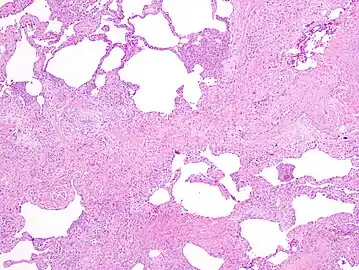

The histologic hallmarks of UIP, as seen in lung tissue under a microscope by a pathologist, are interstitial fibrosis in a "patchwork pattern", honeycomb change and fibroblast foci (see images below).[6] [7]

Appearance of usual interstitial pneumonia (UIP) in a surgical lung biopsy at low magnification. The tissue is stained with hematoxylin (purple dye) and eosin (pink dye) to make it visible. The pink areas in this picture represent lung fibrosis (collagen stains pink). Note the "patchwork" (quilt-like) pattern of the fibrosis.

Appearance of honeycomb change in a surgical lung biopsy at low magnification. The dilated spaces seen here are filled with mucin. Hematoxylin-eosin stain, low magnification.